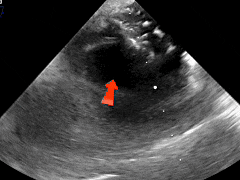

经食道超声可见

第二个缺损5.63mm

术中超声:术中经食道超声可见有两个缺损,分别为8.06mm、5.63mm,和术前超声报告对比有所偏差,两缺损距离约8.48mm。